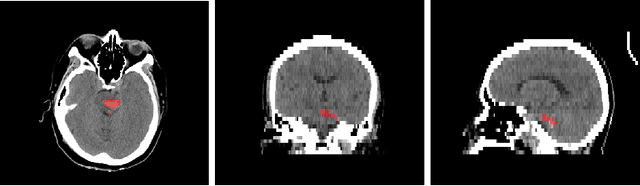

Abstract:Automatic intracranial hemorrhage segmentation in 3D non-contrast head CT (NCCT) scans is significant in clinical practice. Existing hemorrhage segmentation methods usually ignores the anisotropic nature of the NCCT, and are evaluated on different in-house datasets with distinct metrics, making it highly challenging to improve segmentation performance and perform objective comparisons among different methods. The INSTANCE 2022 was a grand challenge held in conjunction with the 2022 International Conference on Medical Image Computing and Computer Assisted Intervention (MICCAI). It is intended to resolve the above-mentioned problems and promote the development of both intracranial hemorrhage segmentation and anisotropic data processing. The INSTANCE released a training set of 100 cases with ground-truth and a validation set with 30 cases without ground-truth labels that were available to the participants. A held-out testing set with 70 cases is utilized for the final evaluation and ranking. The methods from different participants are ranked based on four metrics, including Dice Similarity Coefficient (DSC), Hausdorff Distance (HD), Relative Volume Difference (RVD) and Normalized Surface Dice (NSD). A total of 13 teams submitted distinct solutions to resolve the challenges, making several baseline models, pre-processing strategies and anisotropic data processing techniques available to future researchers. The winner method achieved an average DSC of 0.6925, demonstrating a significant growth over our proposed baseline method. To the best of our knowledge, the proposed INSTANCE challenge releases the first intracranial hemorrhage segmentation benchmark, and is also the first challenge that intended to resolve the anisotropic problem in 3D medical image segmentation, which provides new alternatives in these research fields.